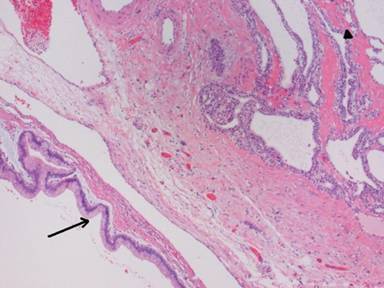

Lesion #2 measured 22 mm in the greatest diameter. Based on sonographic features of lesion #2; a differential diagnosis of likely serous cystadenoma versus other cystic solid lesions (neuroendocrine tumor) was rendered. An EUS guided fine needle aspiration (EUS-FNA) using a 22 G needle of lesion #1 yielded 3 mL of clear viscous fluid with an elevated CEA (203.7 ng/mL) and amylase (17,514 U/L) levels. EUS-FNA cytology was consistent with IPMN. The immediately inferior to the multi-side branch-IPMN location of the lesion #2 precluded safe and uncontaminated advancement of the FNA needle. A subsequent distal pancreatectomy and splenectomy confirmed synchronous microcystic serous cystadenoma and multi-side branch-IPMN (Figure 3). Patient remains asymptomatic at 18-month follow-up.

Figure 3. Histological slide demonstrating synchronous IPMN and serous cystadenoma. The arrow is on the IPMN and the arrowhead is on the serous (microcystic) adenoma. IPMN: tall columnar cells with basal nuclei and abundant mucinous cytoplasm lining a markedly dilated duct. Microcystic serous cystadenoma: multiple small cystic spaces lined by cells with round and central nuclei with clear cytoplasm. (H&E; original magnification: x25) |